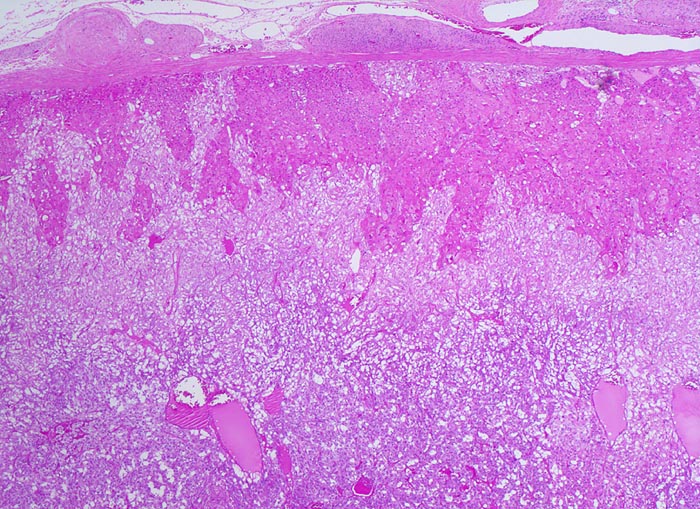

Phaeochromozytom

Nebenniere

Der gefässreiche basophile Tumor ist nicht bekapselt. Der Tumor infiltriert die Nebennierenrinde zungenförmig. Im periadrenalen Weichteilgewebe sind Anschnitte eines peripheren Nerven erkennbar.

Der Patient klagt über rezidivierende Kopfschmerzen seit zirka zwei Monaten. In letzter Zeit hat er Alcacyl genommen, jedoch ohne Erfolg. Die Computertomographie des Abdomens zeigt einen 5cm grossen Tumor im Bereich der rechten Nebenniere. Die Familienanamnese für multiple endokrine Neoplasien (MEN) ist bland.